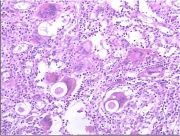

| 2021年12月10日 (五) 13:16 | 16号切片-鳞癌(癌巢)-镜下观2.jpg (文件) |  |

62 KB | Cirno.9 | 基于MsUpload的文件上传 | 1 |

| 2021年12月10日 (五) 13:16 | 16号切片-鳞癌(癌巢)-镜下观1.jpg (文件) |  |

180 KB | Cirno.9 | 基于MsUpload的文件上传 | 1 |